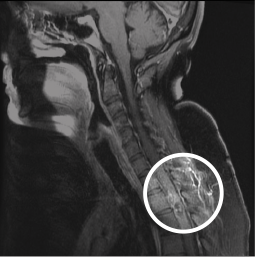

The MRI demonstrated expansion of the spinal cord, starting at C5 and extending to the T9–T10 level (see Figure 1). The MRI showed areas of hemorrhage in the spinal cord most prominent at the T2 level, with multiple serpentine structures consistent with a spinal cord vascular malformation (sAVM) (see Figure 2). The cord edema and expansion presumably reflected venous congestion/hypertension (see Figure 3). A neurosurgery consultation was obtained, and a catheter angiography was performed, localizing the lesion. At the choice of the patient and her family, the patient elected to transfer to another hospital.

Figure 1: Cervical MRI showing expansion of the cervical cord, originating at the C5 level and extending into the lower thoracic spine. The most prominent areas of hemorrhage are in the T2– T3 levels, with multiple serpentine structures.